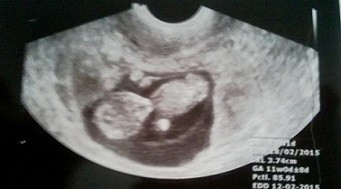

Już, już :-)a więc wszystko jest w porządku, bobas ma nie całe 4cm :) serducho bije, macha rączkami i nóżkami :) dziś lekarz założył mi kartę ciąży i dostałam skierowanie na badania :) nastepna wizyta 19.08.

A oto mój bobasek :)